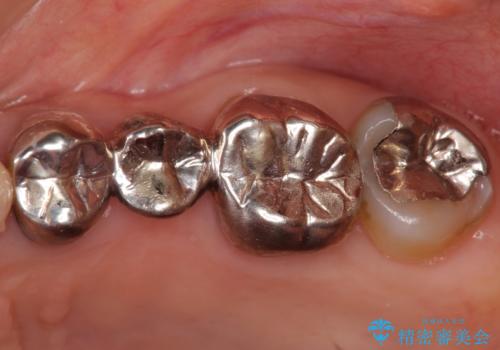

- 20年前に治療した銀歯が壊れ、審美的な修復を希望され来院されました。

銀歯・虫歯を除去し、ジルコニアを咬合再構成を行います。

- 66万円(仮歯・ジルコニアクラウン×6)費用は治療当時の料金となります